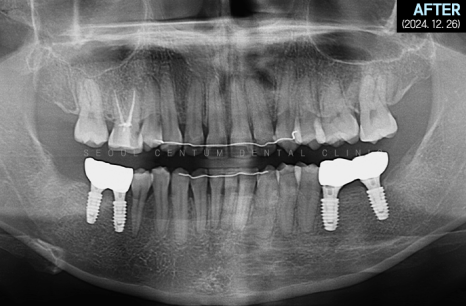

따라서 적정 시기에

CT를 촬영해 치조골 폭과 밀도를

철저하게 분석한 다음 정확한 자리를 선정하고

임플란트 식립을 진행했습니다.

하악 좌측 사랑니 발거 후

임플란트가 필요한 부분들에

픽스처를 견고하게 식립해 드렸습니다.

일정 기간이 지난 후 고정력을 체크하고

지대주에 이어서

크라운까지 예쁘게 수복해 드렸습니다~

크라운으로 감싸고 난 후의 치근단 모습입니다.

정확한 간격으로 견고하게 심어졌으며

주변 치조골 양도 풍부합니다.